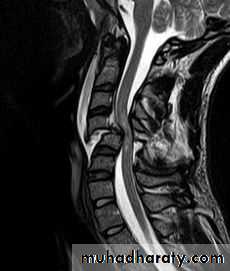

DIAGNOSISX RAY

Anterio posterior X ray radiograph.lateral radiographs with the head in flexion and extension may revealinstability that is not shown in the routine lateral film.

Computed tomography (CT)

and magnetic resonance imaging (MRI).

BURST FRACTURE OF A VERTEBRAL BODY

the compression force thus acts vertically in the line of the vertebral bodies.

The intervertebral disc is forced

In the affected vertebral body, causing a comminuted bursting fracture in which fragments are driven outwards in all directions.